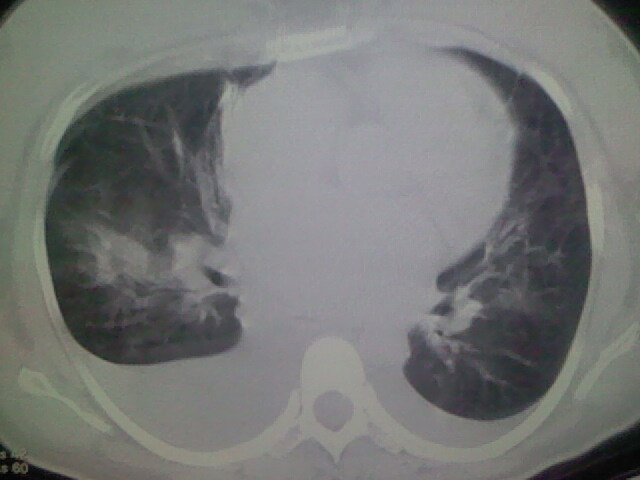

女,24,剖腹产后,突觉胸痛,干咳,不能平卧

肺水肿,双侧胸腔积液,心影增大.考虑妊娠心脏病

风心、心衰。两肺水肿、感染灶及胸水是心衰表现

双肺水肿,双侧胸腔积液,肺梗死不能排除